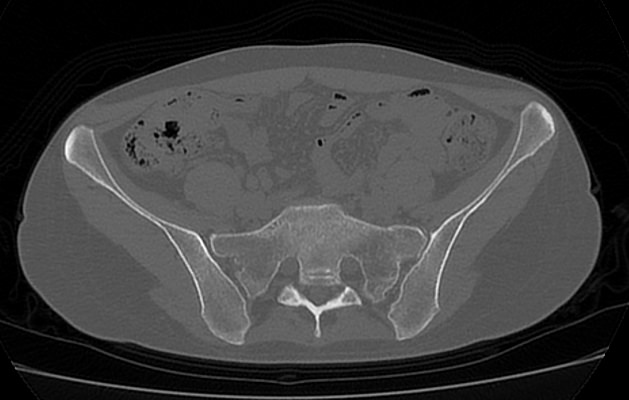

Для диагностики патологии костей таза применяются рентгенологические методы исследования, так как кости хорошо поглощают рентгеновские лучи и поэтому ярко видны на снимках. Современным наиболее информативным способом оценки состояния костных структур таза является мультиспиральная компьютерная томография. По сравнению с обычным рентгеном, когда изображения костей на снимках получается только в одной плоскости и накладывается друг на друга, мультиспиральная КТ позволяет получать послойные изображения в различных плоскостях. Томограф производит множество тончайших срезов исследуемой зоны толщиной от 0,5 мм, которые затем трансформируются при помощи компьютерной обработки данных в трехмерные пространственные модели.

Методика мультиспиральной КТ используется для диагностики переломов костей таза, когда обычный рентген недостаточно информативен. На снимках и трехмерных изображениях хорошо видны фрагменты костных отломков и взаимное расположение костей таза. КТ также назначается перед операцией и после хирургического вмешательства для оценки успешности проведенной операции и для контроля процессов регенерации костной ткани.

Мультиспиральная КТ применяется для диагностики воспалительных и дегенеративно-дистрофических заболеваний тазобедренных суставов, крестцово-подвздошных сочленений, костных структур крестца и копчика.